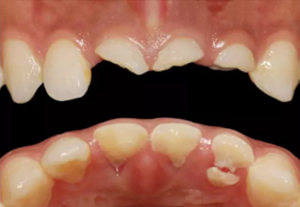

患者,女性,23歲,外傷導(dǎo)致上前牙折斷3天。檢查:中微笑 線;上頜右側(cè)中切牙至左側(cè)側(cè)切牙殘根,不松動,腭側(cè)缺損達(dá)齦下5mm, 牙齦中等厚度,齦緣基本完好。CBCT顯示:根長約11mm,牙根長軸與牙 槽突方向基本一致,唇側(cè)骨板完好、厚度1.0mm,可用骨高度21mm。全身情況良好。

臨床診斷:上頜右側(cè)中切牙至左側(cè)側(cè)切牙冠根折。

圖2 術(shù)前口內(nèi)像